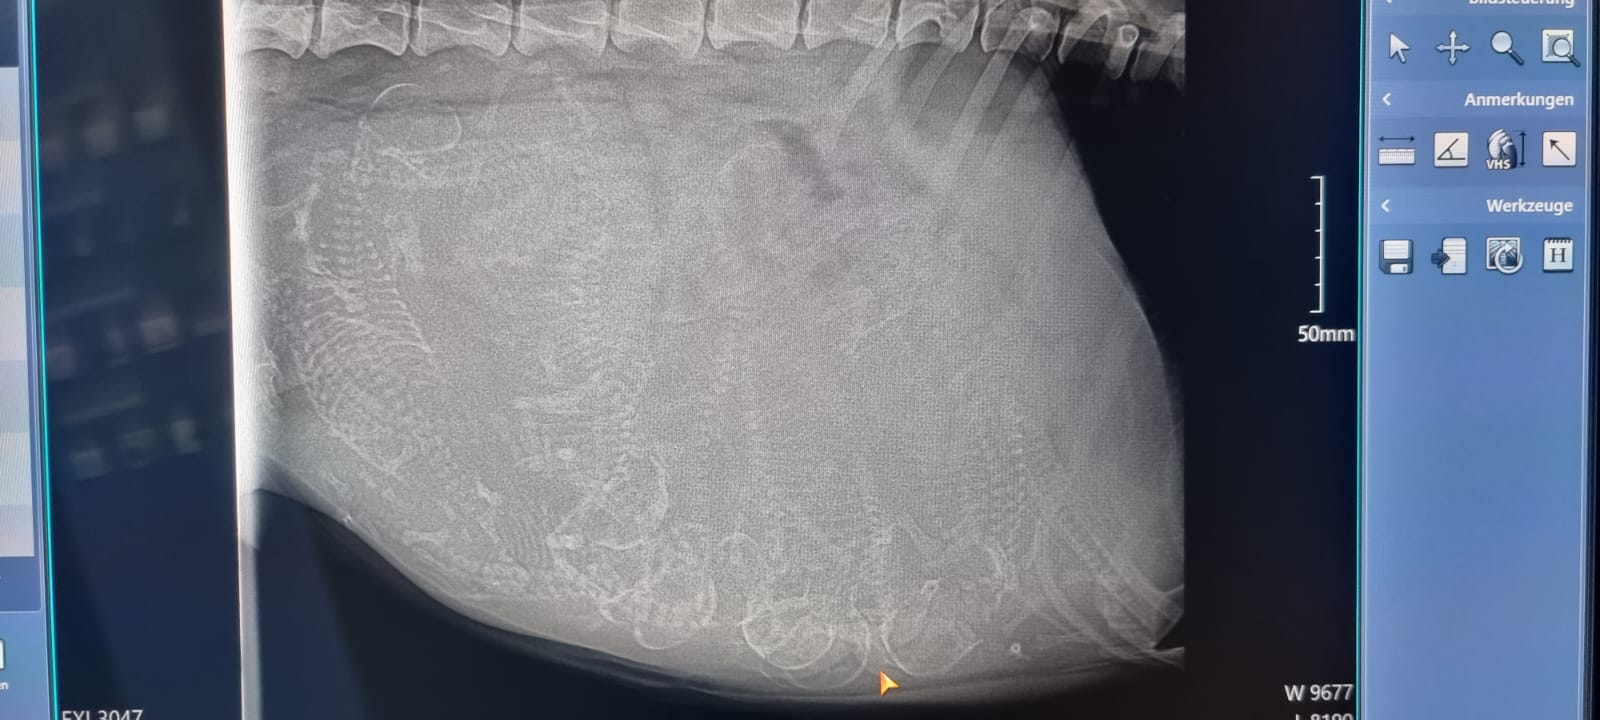

Heute am Tag 55 der Trächtigkeit waren wir mit Bones beim Tierarzt um die obligatorische Röntgenuntersuchung durchführen zu lassen.

Alles ist bestens verlaufen, es werden wohl um die 10 Welpen werden...